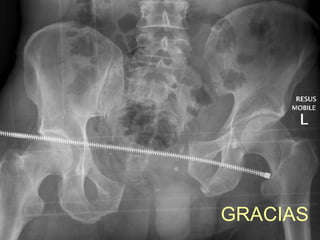

GRACIAS